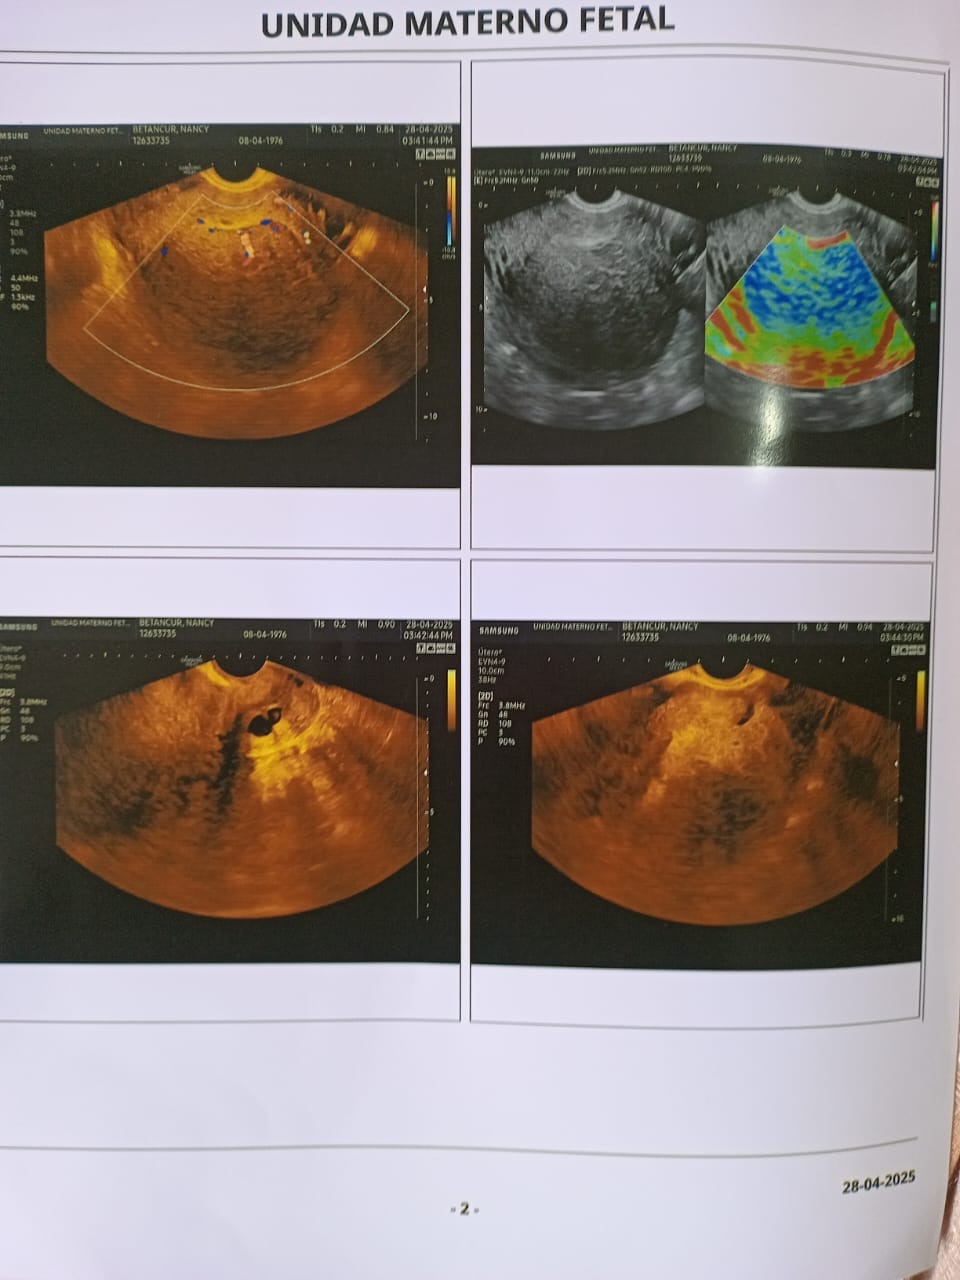

Surgery (Vaginal Hysterectomy)